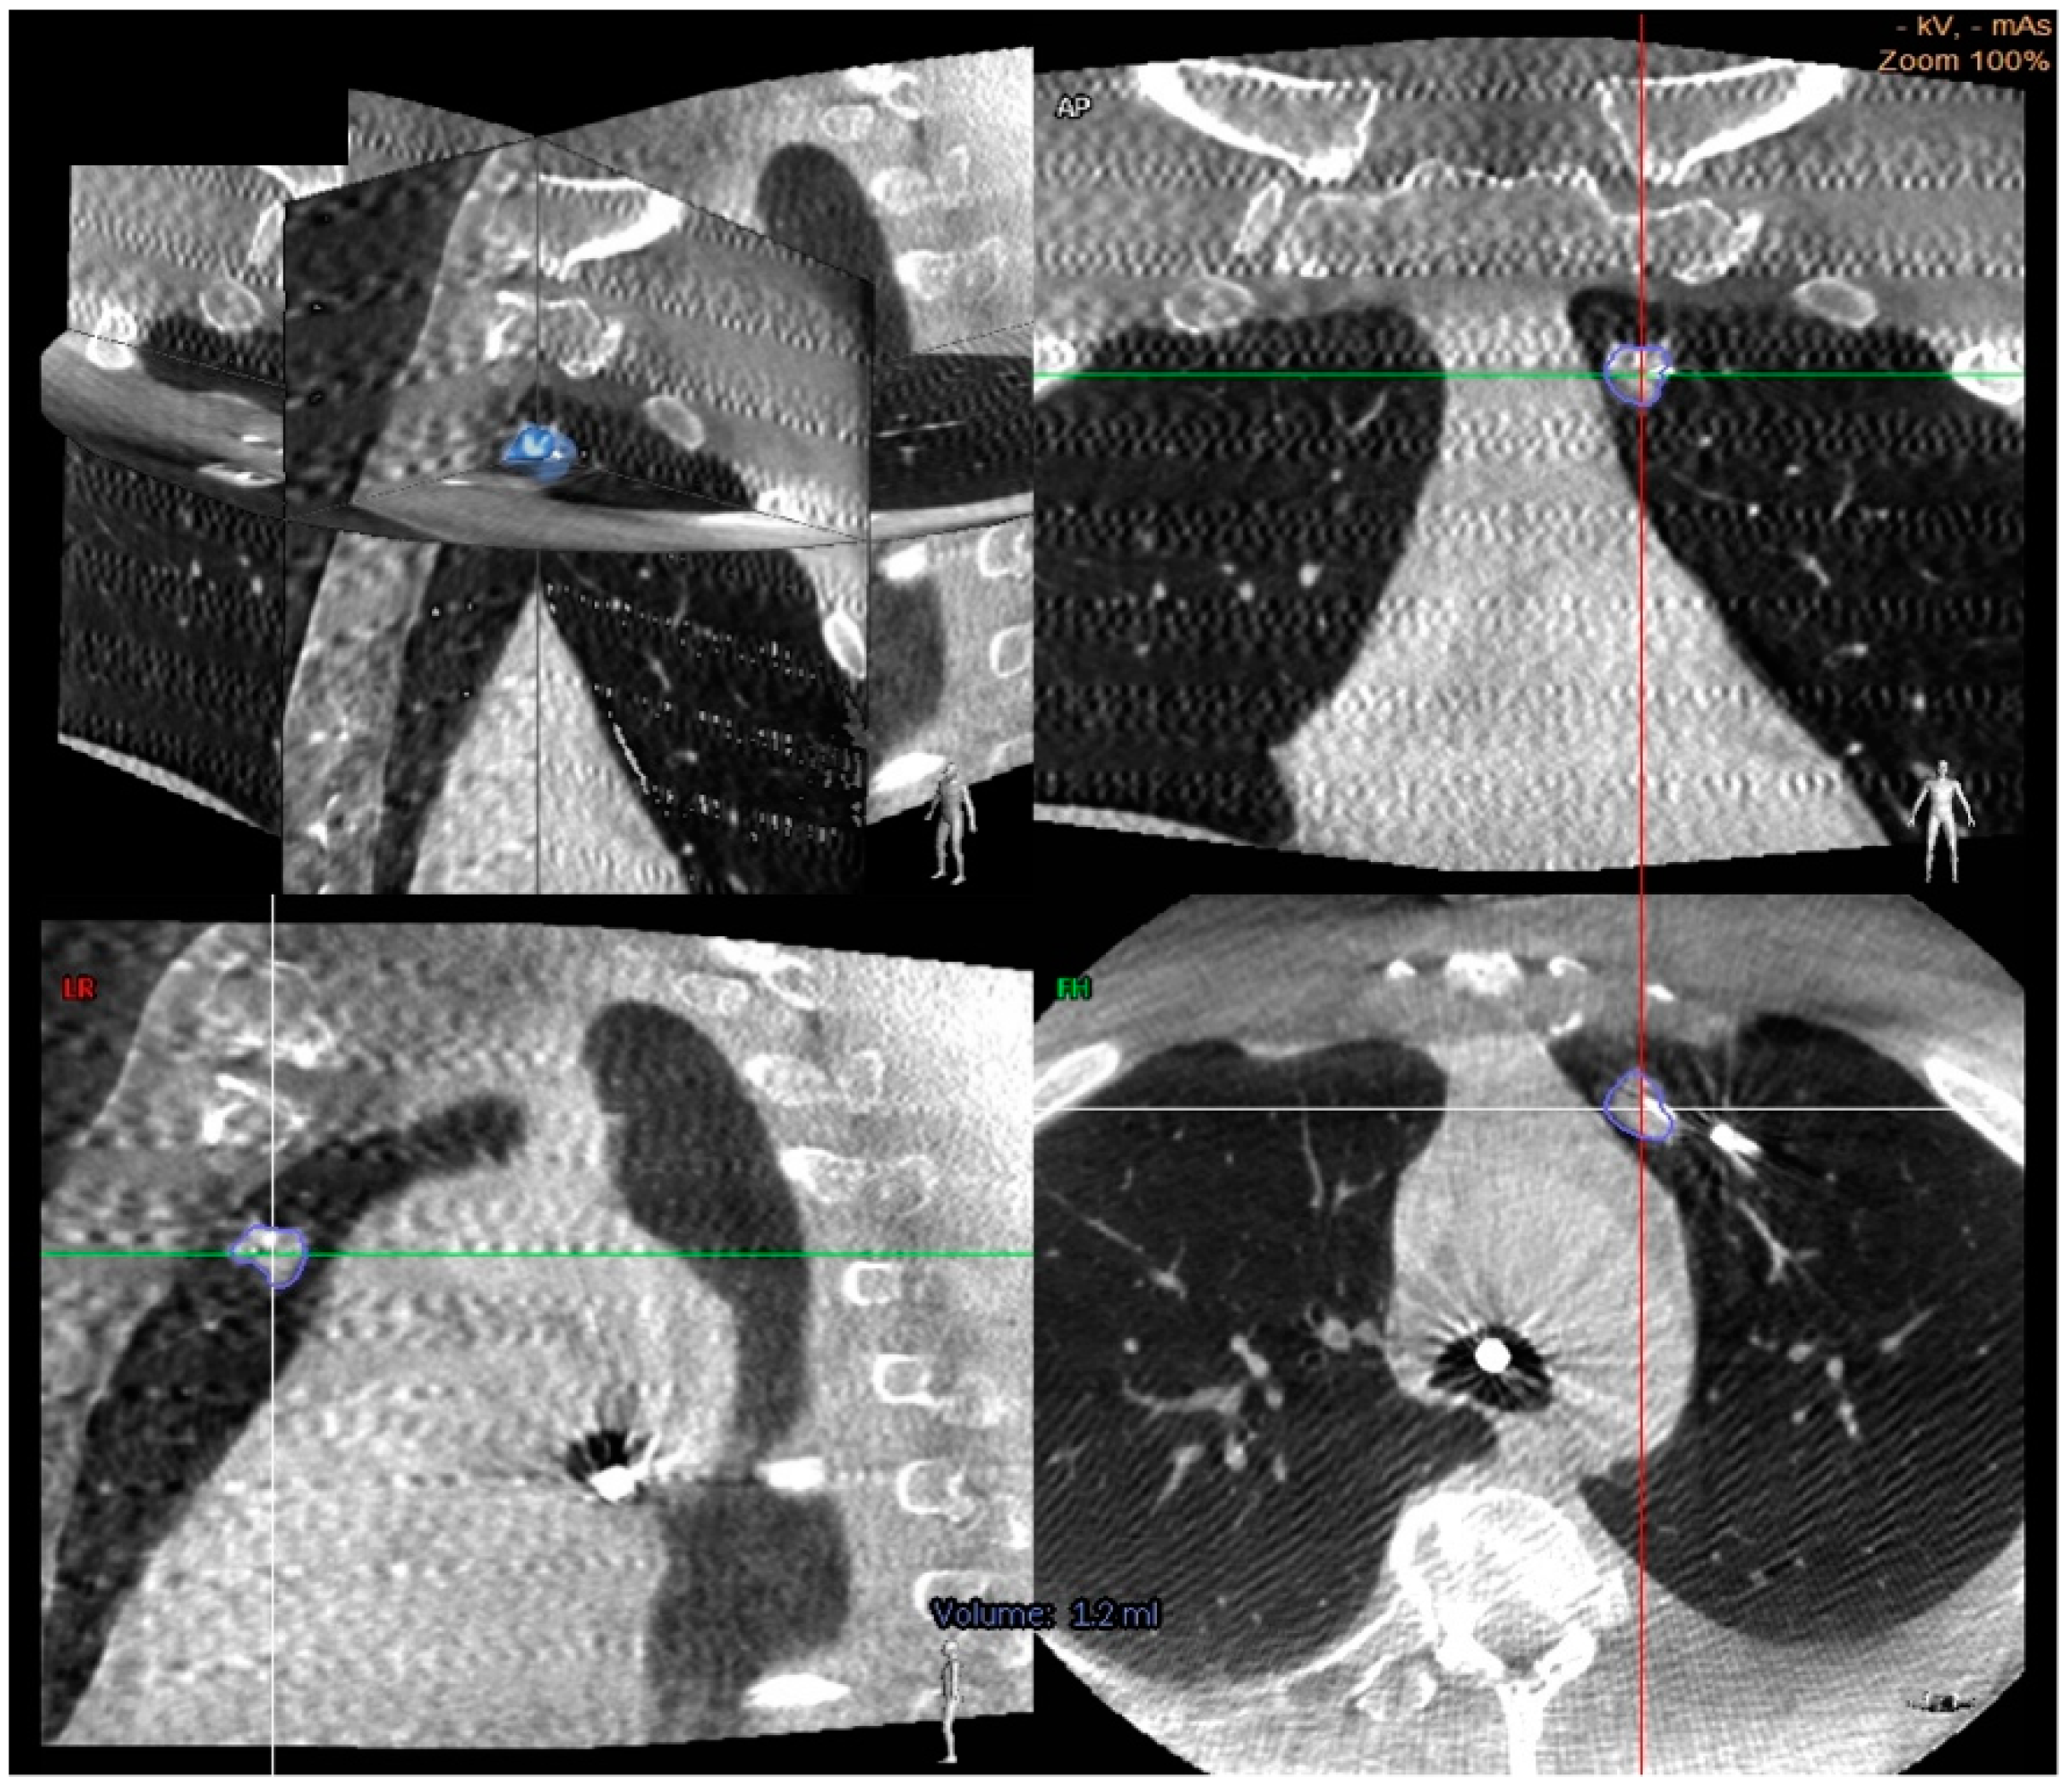

Figure 2.

Cone beam CT images demonstrating a center strike represented by a needle within the nodule in axial, coronal, and sagittal planes [56].

A smaller study of 26 patients looked at “needle in lesion” as a primary outcome to determine the accuracy of F-ENB as confirmed by CBCT. When ENB was performed along with digital tomosynthesis (F-ENB) followed by CBCT once the needle was in the expected location, this resulted in a “needle in lesion” in 72% of cases. Mean nodule size was 13 mm, the majority were in the peripheral third of the chest (83%), and 17% had a bronchus sign. There were no complications. While this was a smaller study, it further elucidated that CBCT can help confirm the needle is intralesional and that F-ENB has high accuracy, even in cases of small peripheral nodules [56].